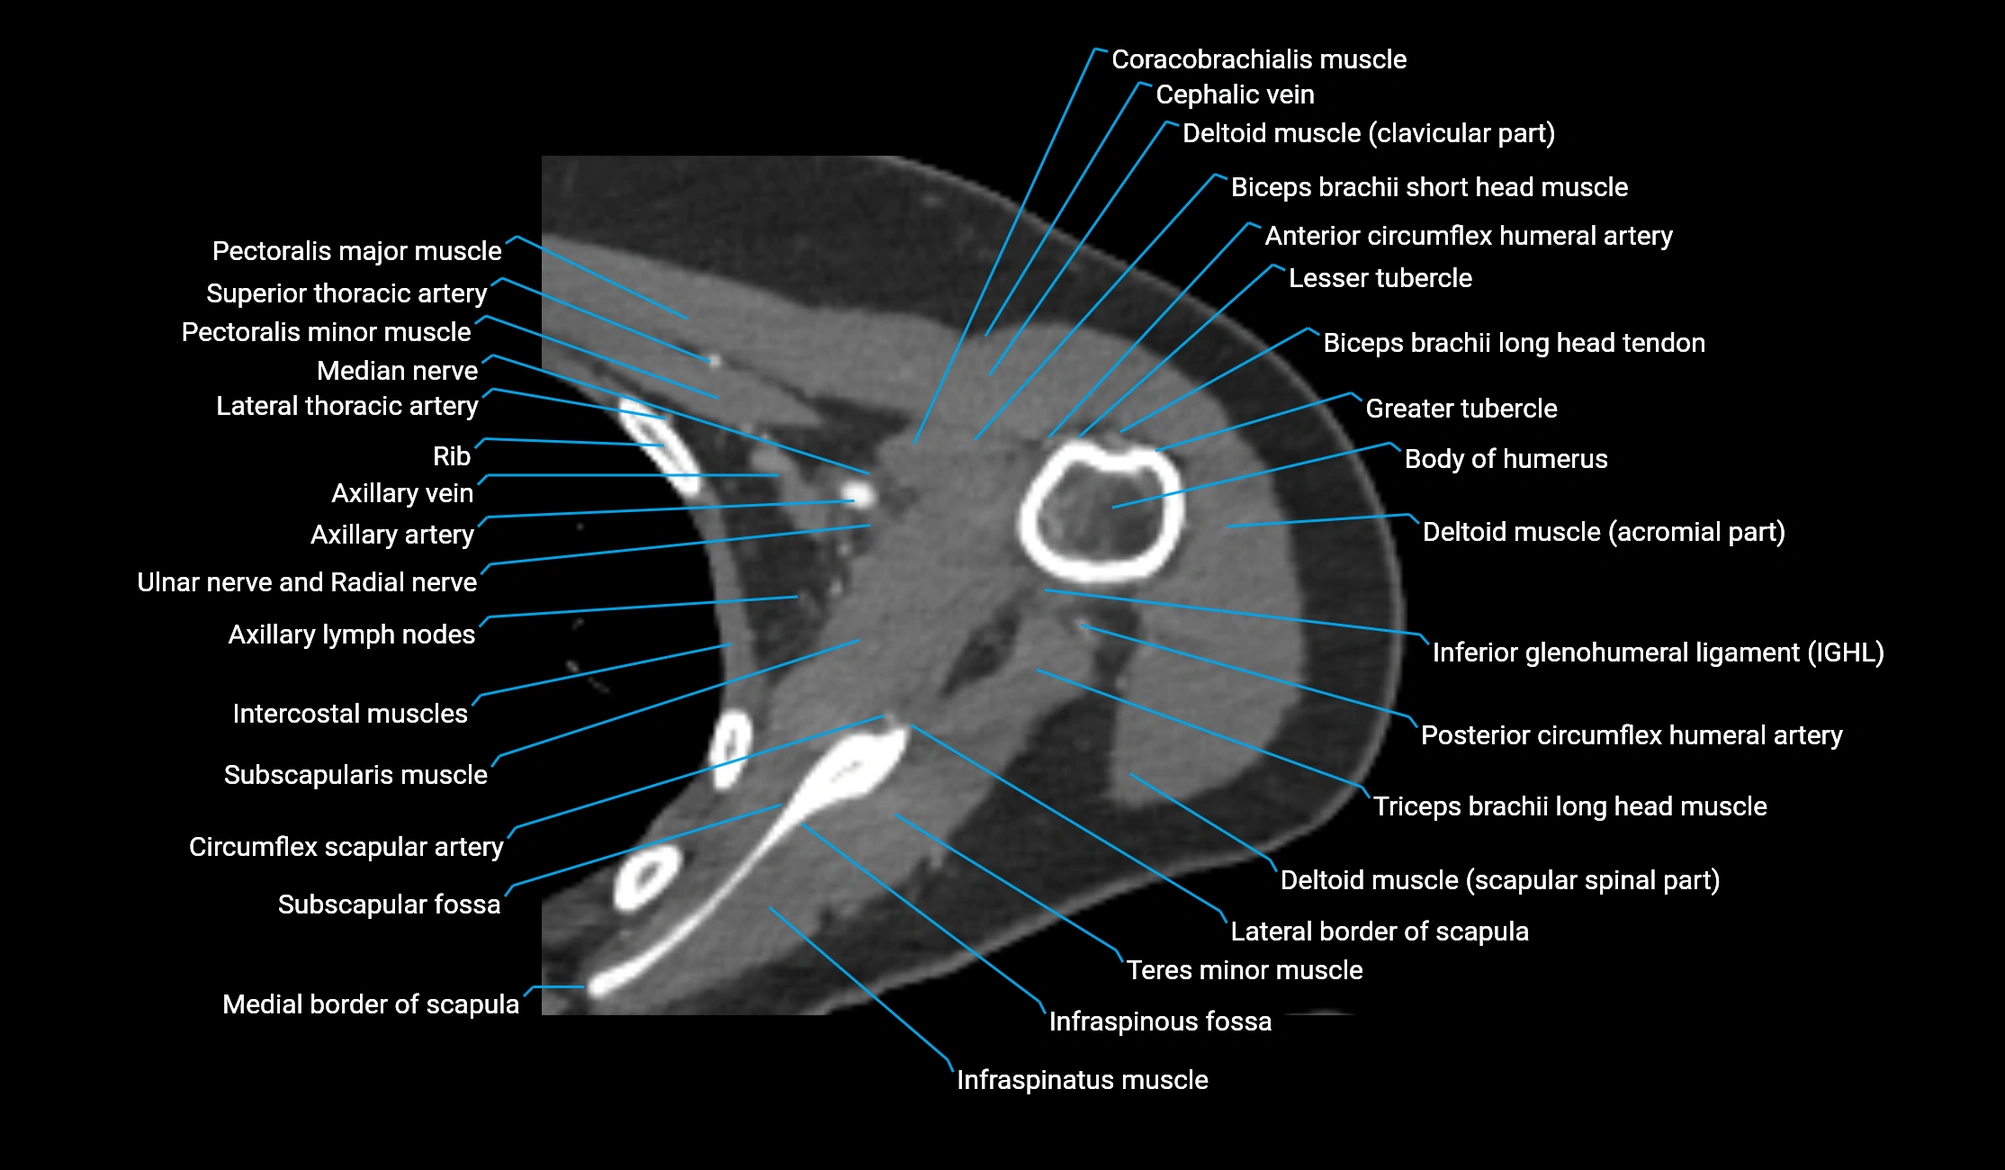

CT image